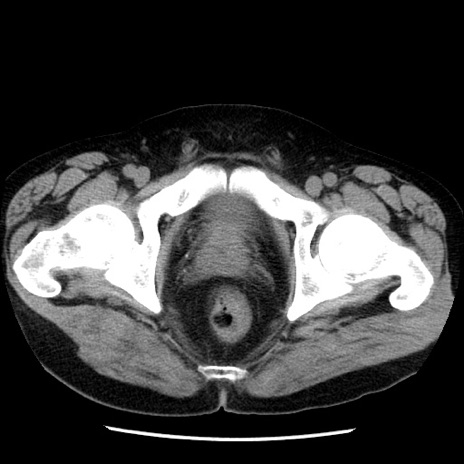

冠状断像

【症例】40歳代男性

【現病歴】2日前から胃痛あり。徐々に周期的な激痛に変化した。本日になっても激痛があるため受診。

【身体所見】意識清明、BT 38-39℃台あり、腹部:膨満、やや硬、右下腹部に圧痛あり。

【データ】WBC 8500、CRP 23.26